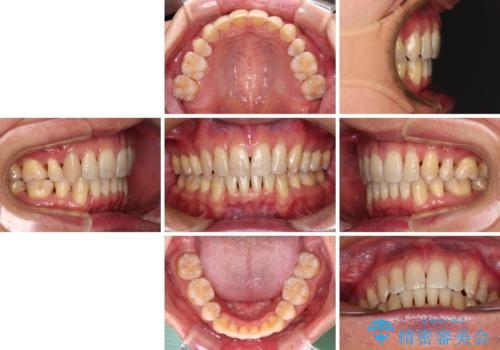

叢生が強い場合、抜歯スペースが叢生を解消するために消費されるため、口元の突出感があまり改善されないことがあります。

今回の治療では、奥歯が前方に傾斜した歯並びだったため、奥に起き上がることで歯列が後方に移動し、横側からも口元が引っ込んだ感じが分かるほど改善されました。